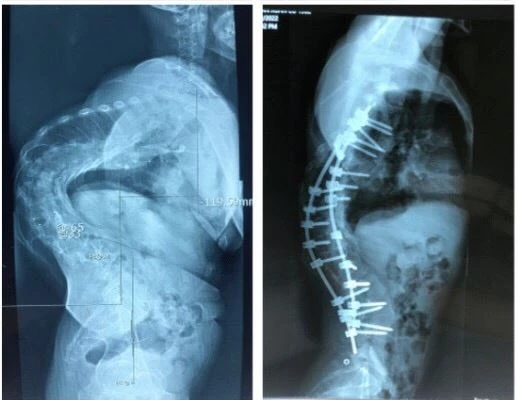

Sau khi đọc tin từ báo chí, bệnh nhân tìm đến BV Trung ương Quân đội 108. Qua các hình ảnh X-quang và tình trạng thực tế của bệnh nhân, các bác sĩ (BS) xác định đây là một ca bệnh đặc biệt khó, góc vẹo rất lớn kèm theo gù cũng rất lớn (trên 100 độ).

| Phim chụp xquang trước và sau phẫu thuật nắn chỉnh gù. Ảnh: BV Trung ương Quân đội 108 |

Nghiên cứu y văn và những kinh nghiệm trước đây, các BS quyết định phẫu thuật cho bệnh nhân với 2 thì mổ. Thì thứ nhất đi lối trước, cắt xương sườn, vén phổi, cắt tối đa được 4 đĩa đệm để làm lỏng cột sống. Sau đó lắp khung Halo kéo dãn trên giường nghiêng 30 độ, trong thời gian 3 tuần, với cân nặng tăng dần đến lúc đạt mức tối đa là 50% cân nặng của bệnh nhân. Thì thứ 2, đi lối sau, bắt vít nắn chỉnh vẹo.

Do thời gian mổ dài, kĩ thuật khó, nhiều nguy cơ tai biến biến chứng nên cuộc đại phẫu cân não kéo dài nhiều tiếng. Sau mổ, hình thể bệnh nhân đã gần như bình thường, chiều cao tăng thêm vài cm.